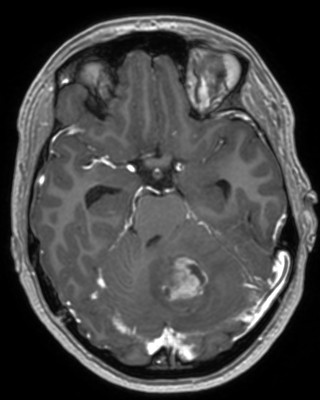

Figure 6: Qualitative evaluation on the RLS dataset. The top row depicts a 33%percent3333\%33 % low-dose sample, where the yellow zoom highlights the lesion. The bottom row shows a case with a 10%percent1010\%10 % real low-dose image and the lesion is marked by the yellow circles.

Refer to captionRefer to caption𝐱PCsubscript𝐱PC\mathbf{x}_{\mathrm{PC}}bold_x start_POSTSUBSCRIPT roman_PC end_POSTSUBSCRIPTRefer to captionRefer to caption𝐱LDsubscript𝐱LD\mathbf{x}_{\mathrm{LD}}bold_x start_POSTSUBSCRIPT roman_LD end_POSTSUBSCRIPTRefer to captionRefer to caption𝐱SDsubscript𝐱SD\mathbf{x}_{\mathrm{SD}}bold_x start_POSTSUBSCRIPT roman_SD end_POSTSUBSCRIPTRefer to captionRefer to captionAm-3D [14]Refer to captionRefer to captionPa-2.5D [8]Refer to captionRefer to caption𝐱~SDsubscript~𝐱SD\tilde{\mathbf{x}}_{\mathrm{SD}}over~ start_ARG bold_x end_ARG start_POSTSUBSCRIPT roman_SD end_POSTSUBSCRIPT (ours)ptPhilips Achieva 3TGadobutrol dLD=0.10subscript𝑑LD0.10d_{\mathrm{LD}}=0.10italic_d start_POSTSUBSCRIPT roman_LD end_POSTSUBSCRIPT = 0.10ptPhilips Ingenia 1.5TGadoterate dLD=0.33subscript𝑑LD0.33d_{\mathrm{LD}}=0.33italic_d start_POSTSUBSCRIPT roman_LD end_POSTSUBSCRIPT = 0.33Refer to captionRefer to caption𝐱PCsubscript𝐱PC\mathbf{x}_{\mathrm{PC}}bold_x start_POSTSUBSCRIPT roman_PC end_POSTSUBSCRIPTRefer to captionRefer to caption𝐱LDsubscript𝐱LD\mathbf{x}_{\mathrm{LD}}bold_x start_POSTSUBSCRIPT roman_LD end_POSTSUBSCRIPTRefer to captionRefer to caption𝐱SDsubscript𝐱SD\mathbf{x}_{\mathrm{SD}}bold_x start_POSTSUBSCRIPT roman_SD end_POSTSUBSCRIPTRefer to captionRefer to captionAm-3D [14]Refer to captionRefer to captionPa-2.5D [8]Refer to captionRefer to caption𝐱~SDsubscript~𝐱SD\tilde{\mathbf{x}}_{\mathrm{SD}}over~ start_ARG bold_x end_ARG start_POSTSUBSCRIPT roman_SD end_POSTSUBSCRIPT (ours)ptPhilips Achieva 3TGadobutrol dLD=0.10subscript𝑑LD0.10d_{\mathrm{LD}}=0.10italic_d start_POSTSUBSCRIPT roman_LD end_POSTSUBSCRIPT = 0.10ptPhilips Ingenia 1.5TGadoterate dLD=0.33subscript𝑑LD0.33d_{\mathrm{LD}}=0.33italic_d start_POSTSUBSCRIPT roman_LD end_POSTSUBSCRIPT = 0.33Refer to captionRefer to caption𝐱PCsubscript𝐱PC\mathbf{x}_{\mathrm{PC}}bold_x start_POSTSUBSCRIPT roman_PC end_POSTSUBSCRIPTRefer to captionRefer to caption𝐱LDsubscript𝐱LD\mathbf{x}_{\mathrm{LD}}bold_x start_POSTSUBSCRIPT roman_LD end_POSTSUBSCRIPTRefer to captionRefer to caption𝐱SDsubscript𝐱SD\mathbf{x}_{\mathrm{SD}}bold_x start_POSTSUBSCRIPT roman_SD end_POSTSUBSCRIPTRefer to captionRefer to captionAm-3D [14]Refer to captionRefer to captionPa-2.5D [8]Refer to captionRefer to caption𝐱~SDsubscript~𝐱SD\tilde{\mathbf{x}}_{\mathrm{SD}}over~ start_ARG bold_x end_ARG start_POSTSUBSCRIPT roman_SD end_POSTSUBSCRIPT (ours)ptPhilips Achieva 3TGadobutrol dLD=0.10subscript𝑑LD0.10d_{\mathrm{LD}}=0.10italic_d start_POSTSUBSCRIPT roman_LD end_POSTSUBSCRIPT = 0.10ptPhilips Ingenia 1.5TGadoterate dLD=0.33subscript𝑑LD0.33d_{\mathrm{LD}}=0.33italic_d start_POSTSUBSCRIPT roman_LD end_POSTSUBSCRIPT = 0.33Refer to captionRefer to caption𝐱PCsubscript𝐱PC\mathbf{x}_{\mathrm{PC}}bold_x start_POSTSUBSCRIPT roman_PC end_POSTSUBSCRIPTRefer to captionRefer to caption𝐱LDsubscript𝐱LD\mathbf{x}_{\mathrm{LD}}bold_x start_POSTSUBSCRIPT roman_LD end_POSTSUBSCRIPTRefer to captionRefer to caption𝐱SDsubscript𝐱SD\mathbf{x}_{\mathrm{SD}}bold_x start_POSTSUBSCRIPT roman_SD end_POSTSUBSCRIPTRefer to captionRefer to captionAm-3D [14]Refer to captionRefer to captionPa-2.5D [8]Refer to captionRefer to caption𝐱~SDsubscript~𝐱SD\tilde{\mathbf{x}}_{\mathrm{SD}}over~ start_ARG bold_x end_ARG start_POSTSUBSCRIPT roman_SD end_POSTSUBSCRIPT (ours)ptPhilips Achieva 3TGadobutrol dLD=0.10subscript𝑑LD0.10d_{\mathrm{LD}}=0.10italic_d start_POSTSUBSCRIPT roman_LD end_POSTSUBSCRIPT = 0.10ptPhilips Ingenia 1.5TGadoterate dLD=0.33subscript𝑑LD0.33d_{\mathrm{LD}}=0.33italic_d start_POSTSUBSCRIPT roman_LD end_POSTSUBSCRIPT = 0.33Refer to captionRefer to caption𝐱PCsubscript𝐱PC\mathbf{x}_{\mathrm{PC}}bold_x start_POSTSUBSCRIPT roman_PC end_POSTSUBSCRIPTRefer to captionRefer to caption𝐱LDsubscript𝐱LD\mathbf{x}_{\mathrm{LD}}bold_x start_POSTSUBSCRIPT roman_LD end_POSTSUBSCRIPTRefer to captionRefer to caption𝐱SDsubscript𝐱SD\mathbf{x}_{\mathrm{SD}}bold_x start_POSTSUBSCRIPT roman_SD end_POSTSUBSCRIPTRefer to captionRefer to captionAm-3D [14]Refer to captionRefer to captionPa-2.5D [8]Refer to captionRefer to caption𝐱~SDsubscript~𝐱SD\tilde{\mathbf{x}}_{\mathrm{SD}}over~ start_ARG bold_x end_ARG start_POSTSUBSCRIPT roman_SD end_POSTSUBSCRIPT (ours)ptPhilips Achieva 3TGadobutrol dLD=0.10subscript𝑑LD0.10d_{\mathrm{LD}}=0.10italic_d start_POSTSUBSCRIPT roman_LD end_POSTSUBSCRIPT = 0.10ptPhilips Ingenia 1.5TGadoterate dLD=0.33subscript𝑑LD0.33d_{\mathrm{LD}}=0.33italic_d start_POSTSUBSCRIPT roman_LD end_POSTSUBSCRIPT = 0.33Refer to captionRefer to caption𝐱PCsubscript𝐱PC\mathbf{x}_{\mathrm{PC}}bold_x start_POSTSUBSCRIPT roman_PC end_POSTSUBSCRIPTRefer to captionRefer to caption𝐱LDsubscript𝐱LD\mathbf{x}_{\mathrm{LD}}bold_x start_POSTSUBSCRIPT roman_LD end_POSTSUBSCRIPTRefer to captionRefer to caption𝐱SDsubscript𝐱SD\mathbf{x}_{\mathrm{SD}}bold_x start_POSTSUBSCRIPT roman_SD end_POSTSUBSCRIPTRefer to captionRefer to captionAm-3D [14]Refer to captionRefer to captionPa-2.5D [8]Refer to captionRefer to caption𝐱~SDsubscript~𝐱SD\tilde{\mathbf{x}}_{\mathrm{SD}}over~ start_ARG bold_x end_ARG start_POSTSUBSCRIPT roman_SD end_POSTSUBSCRIPT (ours)ptPhilips Achieva 3TGadobutrol dLD=0.10subscript𝑑LD0.10d_{\mathrm{LD}}=0.10italic_d start_POSTSUBSCRIPT roman_LD end_POSTSUBSCRIPT = 0.10ptPhilips Ingenia 1.5TGadoterate dLD=0.33subscript𝑑LD0.33d_{\mathrm{LD}}=0.33italic_d start_POSTSUBSCRIPT roman_LD end_POSTSUBSCRIPT = 0.33Refer to captionRefer to caption𝐱PCsubscript𝐱PC\mathbf{x}_{\mathrm{PC}}bold_x start_POSTSUBSCRIPT roman_PC end_POSTSUBSCRIPTRefer to captionRefer to caption𝐱LDsubscript𝐱LD\mathbf{x}_{\mathrm{LD}}bold_x start_POSTSUBSCRIPT roman_LD end_POSTSUBSCRIPTRefer to captionRefer to caption𝐱SDsubscript𝐱SD\mathbf{x}_{\mathrm{SD}}bold_x start_POSTSUBSCRIPT roman_SD end_POSTSUBSCRIPTRefer to captionRefer to captionAm-3D [14]Refer to captionRefer to captionPa-2.5D [8]Refer to captionRefer to caption𝐱~SDsubscript~𝐱SD\tilde{\mathbf{x}}_{\mathrm{SD}}over~ start_ARG bold_x end_ARG start_POSTSUBSCRIPT roman_SD end_POSTSUBSCRIPT (ours)ptPhilips Achieva 3TGadobutrol dLD=0.10subscript𝑑LD0.10d_{\mathrm{LD}}=0.10italic_d start_POSTSUBSCRIPT roman_LD end_POSTSUBSCRIPT = 0.10ptPhilips Ingenia 1.5TGadoterate dLD=0.33subscript𝑑LD0.33d_{\mathrm{LD}}=0.33italic_d start_POSTSUBSCRIPT roman_LD end_POSTSUBSCRIPT = 0.33

A qualitative comparison of RLD test samples is shown in Figure 6. The required skull stripping and non-linear intensity normalization of Am-3D are readily apparent. Thus, a quantitative comparison to the target 𝐱SDsubscript𝐱SD\mathbf{x}_{\mathrm{SD}}bold_x start_POSTSUBSCRIPT roman_SD end_POSTSUBSCRIPT is not reasonable. Nevertheless, the CE signal strength in pathological regions (highlighted by the yellow circles) is well visible despite too smooth output images. The internal morphology and the border delineation also exhibit blurring. Pa-2.5D yields better image quality but the contrast strength in pathological regions is not well captured. In particular, the contrast signal overshoots for the 33%percent3333\%33 % low-dose scan in the first row and undershoots for the 10%percent1010\%10 % scan at the bottom, although the training dataset contains low-dose images at both dose levels. Our approach yields the highest image quality and predicts the contrast enhancement more accurately due to the focus on the enhancement signal and the conditional embeddings. As a result, our approach generates CE images preserving the image quality of the inputs by avoiding the synthesis of anatomical or noise patterns.